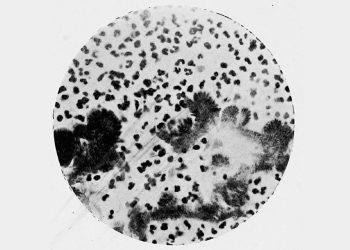

Microscopic image showing a bone cyst under histological evaluation with varying shades of pink and purple.

A microscopic view used in the diagnosis of bone cysts, revealing the cellular composition and structural characteristics of the lesion.